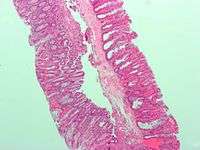

Microvesicular hyperplastic polyp. H&E stain.

Microvesicular hyperplastic polyp. H&E stain. Microvesicular hyperplastic polyp. H&E stain.